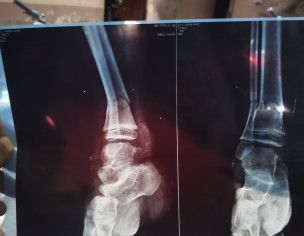

tuqeer sir meri daughter ki leg bone brake ho gai ha.. Ap ya x ray dakh kar batain plaster braber hoa .. Operate ki to zarurat Ki age 7 year ha

pop cast for 5 weeks need no surgery

plaster is enough, can you please send me new Xrays after 2 weeks to see the progress, is this plaster is above knee

plaster